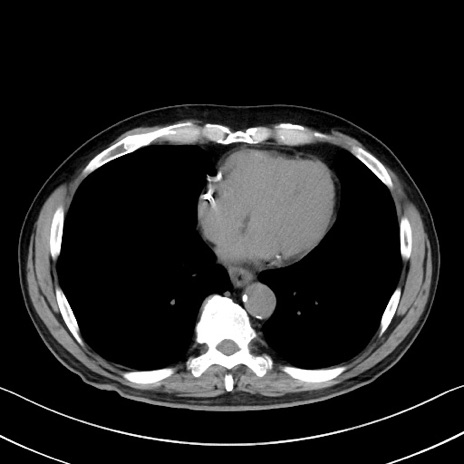

症例35(横断像)

【症例】70歳代 男性

【主訴】腹部膨満、嘔吐

【現病歴】昨日より腹部膨満感出現。本日増悪し、仙痛出現。嘔吐あり、受診。

【既往歴】糖尿病、胆摘後

【身体所見】BP 149/80mmHg、HR 74/min、BT 35.9℃、腹部:膨満、軟、圧痛なし。腸雑音減弱あり。上腹部正中切開瘢痕あり。

【データ】WBC 13500、CRP 1.72